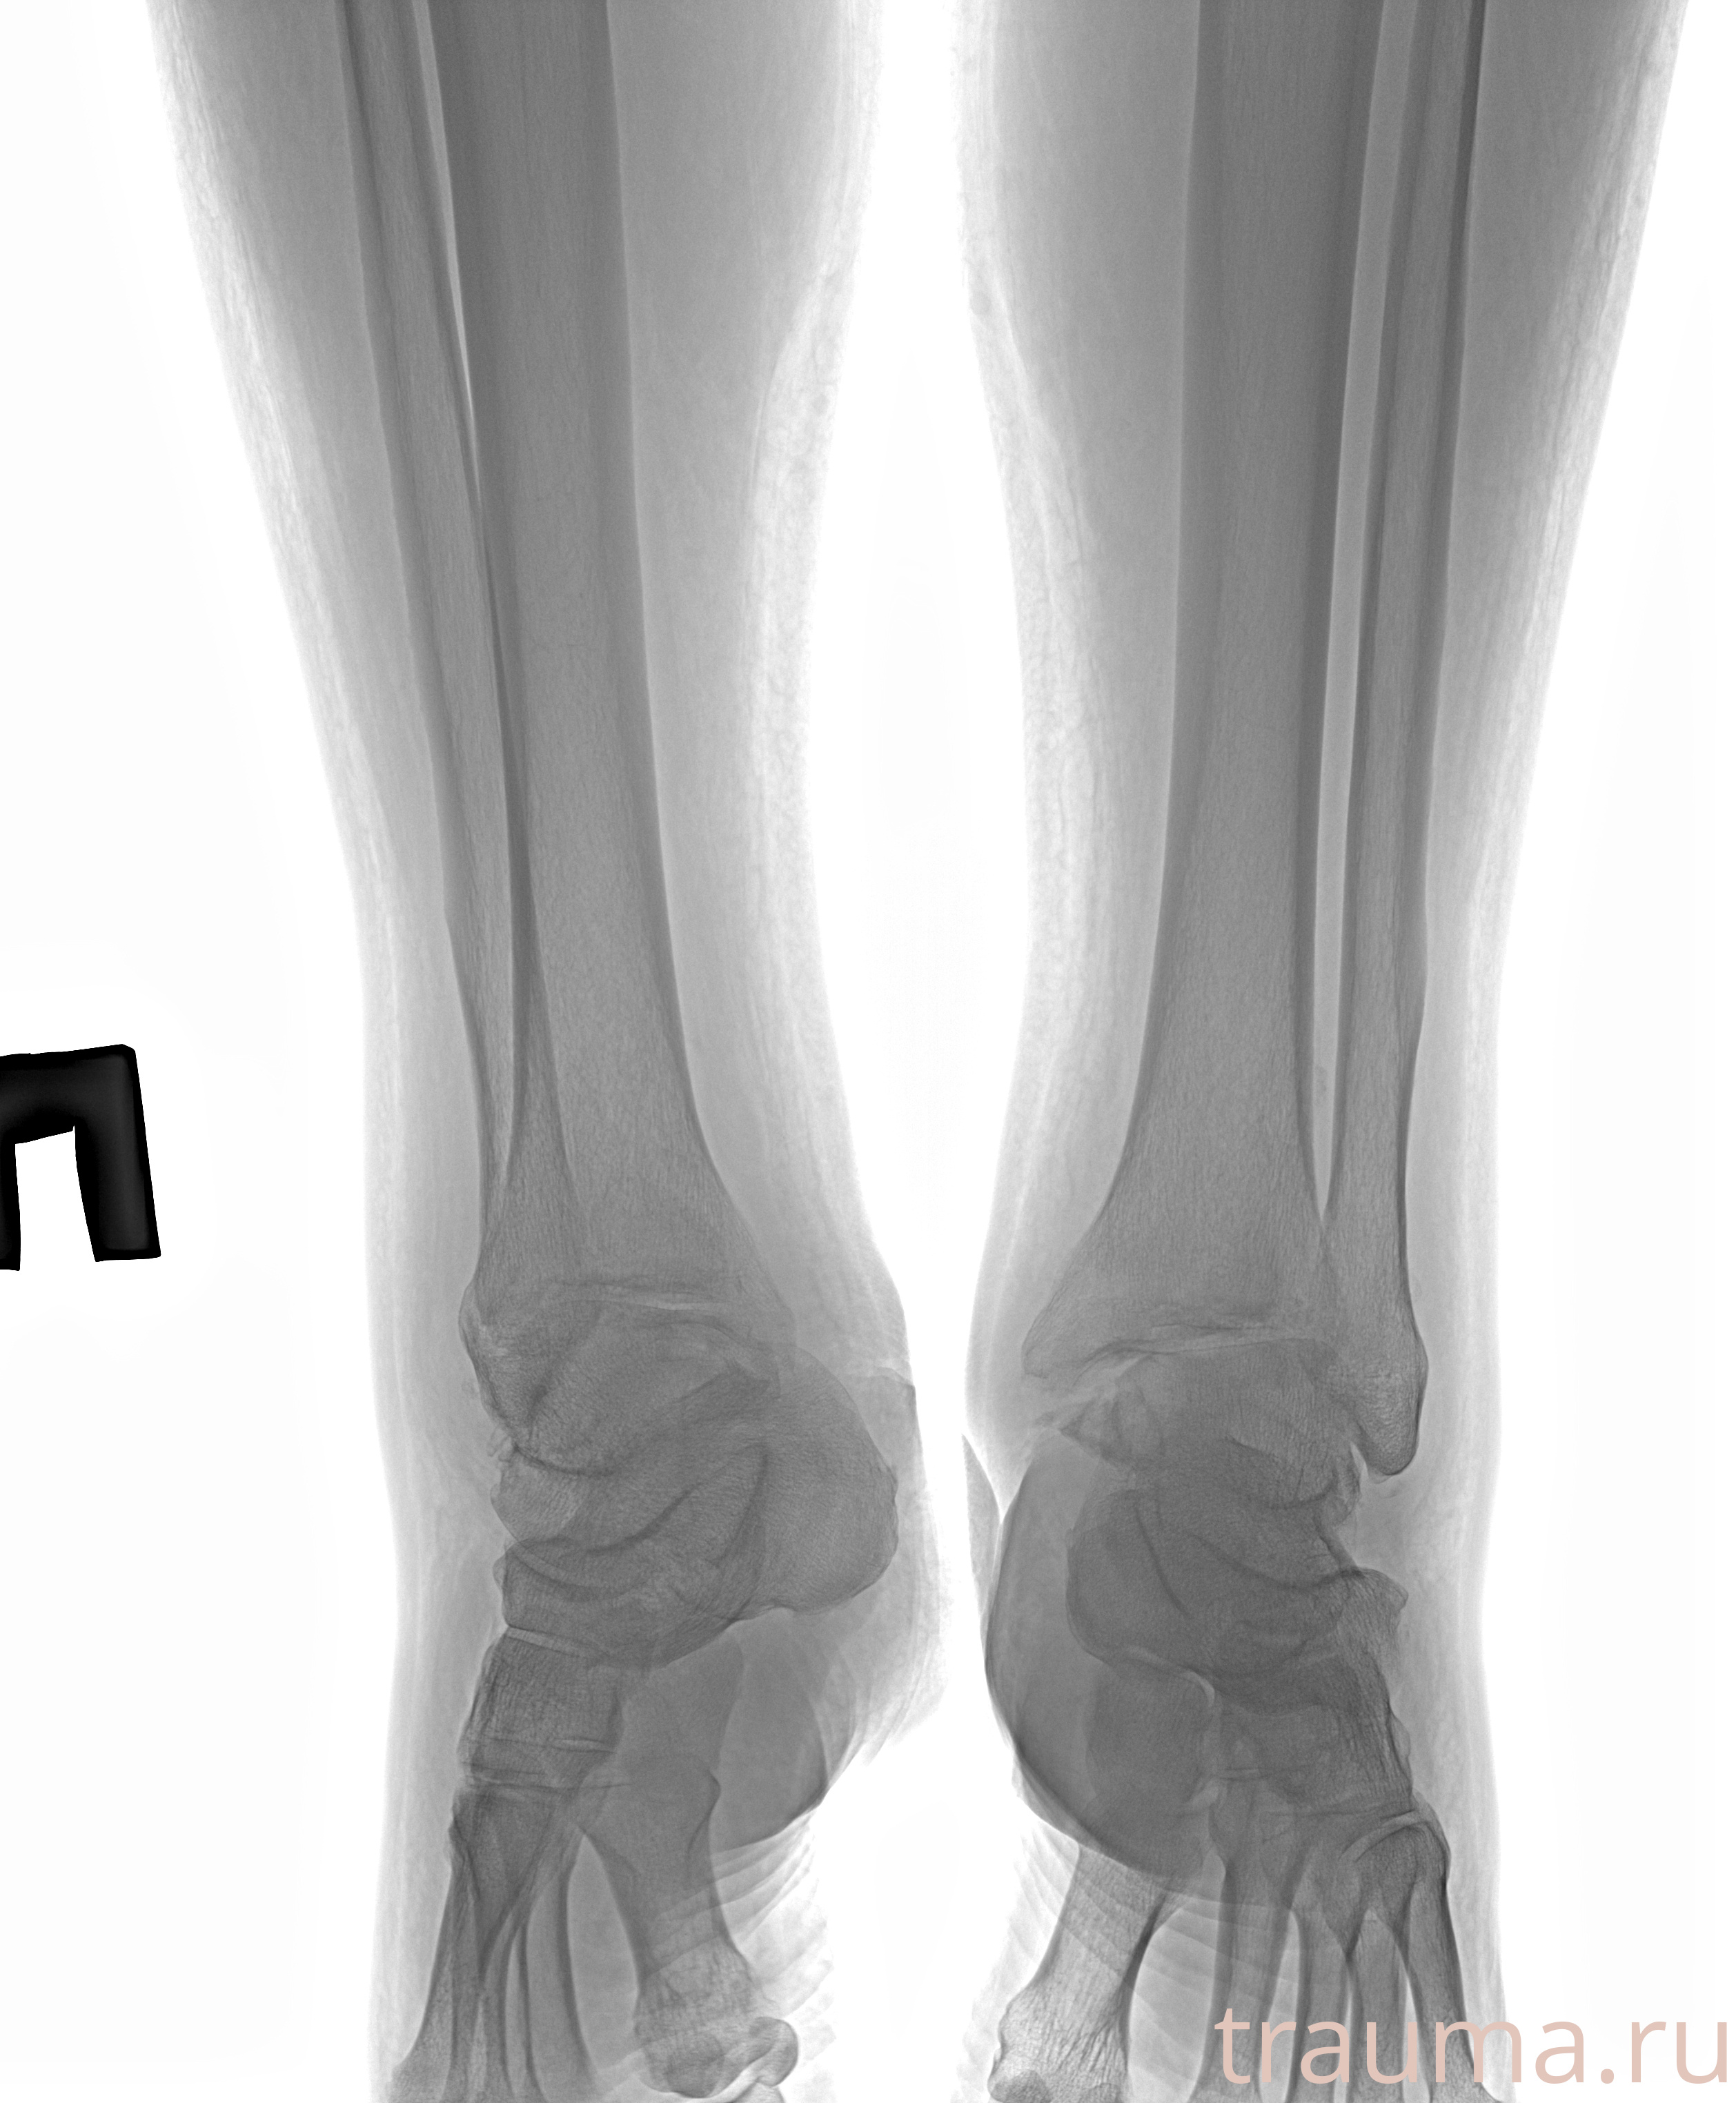

Рентгенограммы

Рентген на дому: по вашему адресу приезжает врач-рентгенолог, травматолог-ортопед с мобильным рентгеновским аппаратом, проводит диагностику травмы или заболевания, делает необходимые рентгенограммы, дает рекомендации по дальнейшему лечению. Получить качественные снимки в домашних условиях возможно благодаря уникальной методике, разработанной МосРентген Центром для института  Склифосовского